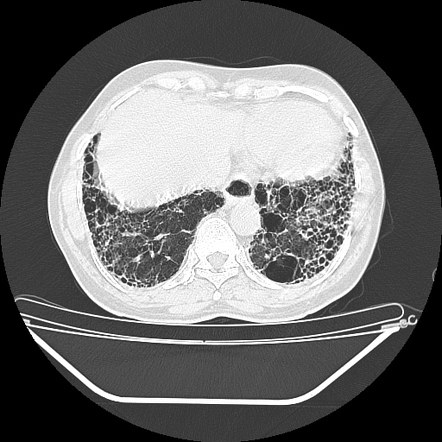

Lymphangioleiomyomatosis (LAM)

Large thin-walled cysts diffusely distributed in the lungs that will eventually replace the entire lung parenchyma.

exclusive to women of child-bearing age, except for TS associated in men

–lymphangiomas and AMLs are commonly associated.

–A/w chylothorax

49 year old woman with a rash on her face. CT chest with multiple thin walled cysts

LAM

a/w renal AMLs and LAD, seen here

Almost exclusively middle aged women although can also occur in TS

p/w exertional dyspnea, recurrent PTX is common